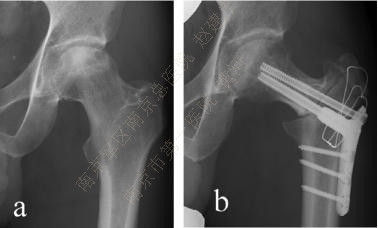

(2) 截骨

ONFH的截骨原则是纠正股骨头半脱位,恢复同心圆结构,减少负重时对坏死区的刺激。

目前临床上常用的截骨有经转子间旋转截骨(transtrochanteric osteotomy ,TRO) 及经转子间弧形内翻截骨curved varus osteotomy (CVO)两种。

TRO根据股骨轴线将股骨头颈向前方或后方旋转,使坏死区的软骨移出负重区,代之以健康的软骨。旋前或旋后取决于侧位片对坏死区的显示,如坏死位于负重区前方,则采用前方旋转截骨,反之同理。Ikemura报道优良率达80%以上。

CVO目的与TRO类似,试图将外侧相对健康的骨与软骨转移至负重区,与TRO相比,CVO能调整的范围较小,但优点是降低了对股骨头血供破坏的风险,对技术的要求也不高。